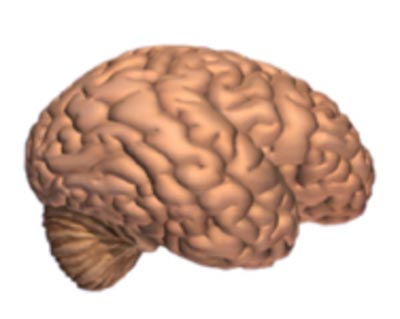

Alzheimer's disease leads to nerve cell death and tissue loss throughout the brain. Over time, the brain shrinks dramatically, affecting nearly all its functions.

These images show:

A brain without the disease.

A brain with advanced Alzheimer's.

How the two brains compare.